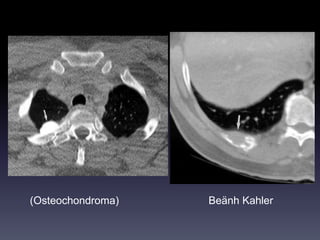

U XÖÔNG &PHAÀN MEÀM

Hình CT

-Huûy, bieán daïng xöông / Toån thöông phaàn

meàm/ Xoùa lôùp môõ ngoøai maøng phoåi (+/-

)

-Caàn khaûo saùt coù caûn quang.

Vai troø CT

-Ñaùnh giaù toát vò trí, möùc ñoä, lieân quan

toån thöông vôùi caùc caáu truùc khaùc ngöïc

(phoåi, maøng phoåi, trung thaát)

(Osteochondroma) Beänh Kahler